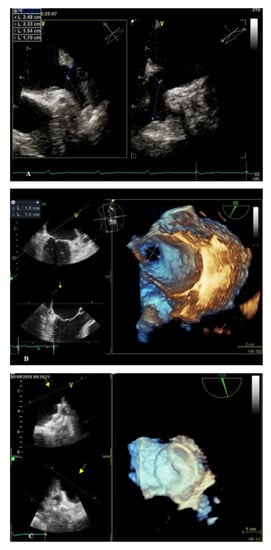

- Nucifora, G.; Faletra, F.F.; Regoli, F.; Pasotti, E.; Pedrazzini, G.; Moccetti, T.; Auricchio, A. Evaluation of the left atrial appendage with real-time 3-dimensional transesophageal echocardiography: Implications for catheter-based left atrial appendage closure. Circ. Cardiovasc. Imaging 2011, 4, 514–523. [Google Scholar] [CrossRef] [PubMed]

- Zhang, J.; Cui, C.Y.; Huang, D.Q.; Liu, Y.Y.; Qin, Y.Y.; Zhang, L.Z.; Liu, L. Evaluation of the left atrial appendage by real time three-dimensional transesophageal echocardiography online. Echocardiography 2018, 35, 991–998. [Google Scholar] [CrossRef] [PubMed]